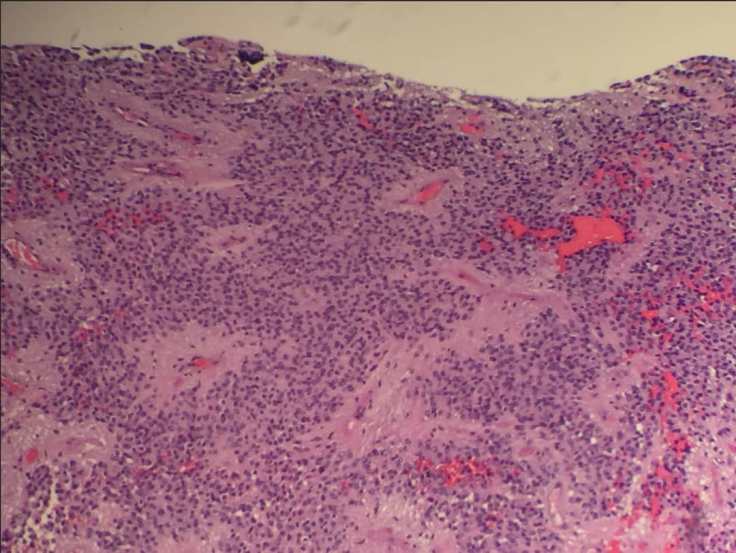

A common histologic finding in ependymomas (shown here) are perivascular pseudo-rosettes characterized by neoplastic ependymal cell nuclei radiating outward from a blood vessel, which creates a pink zone of glial processes immediately surrounding the blood vessels.